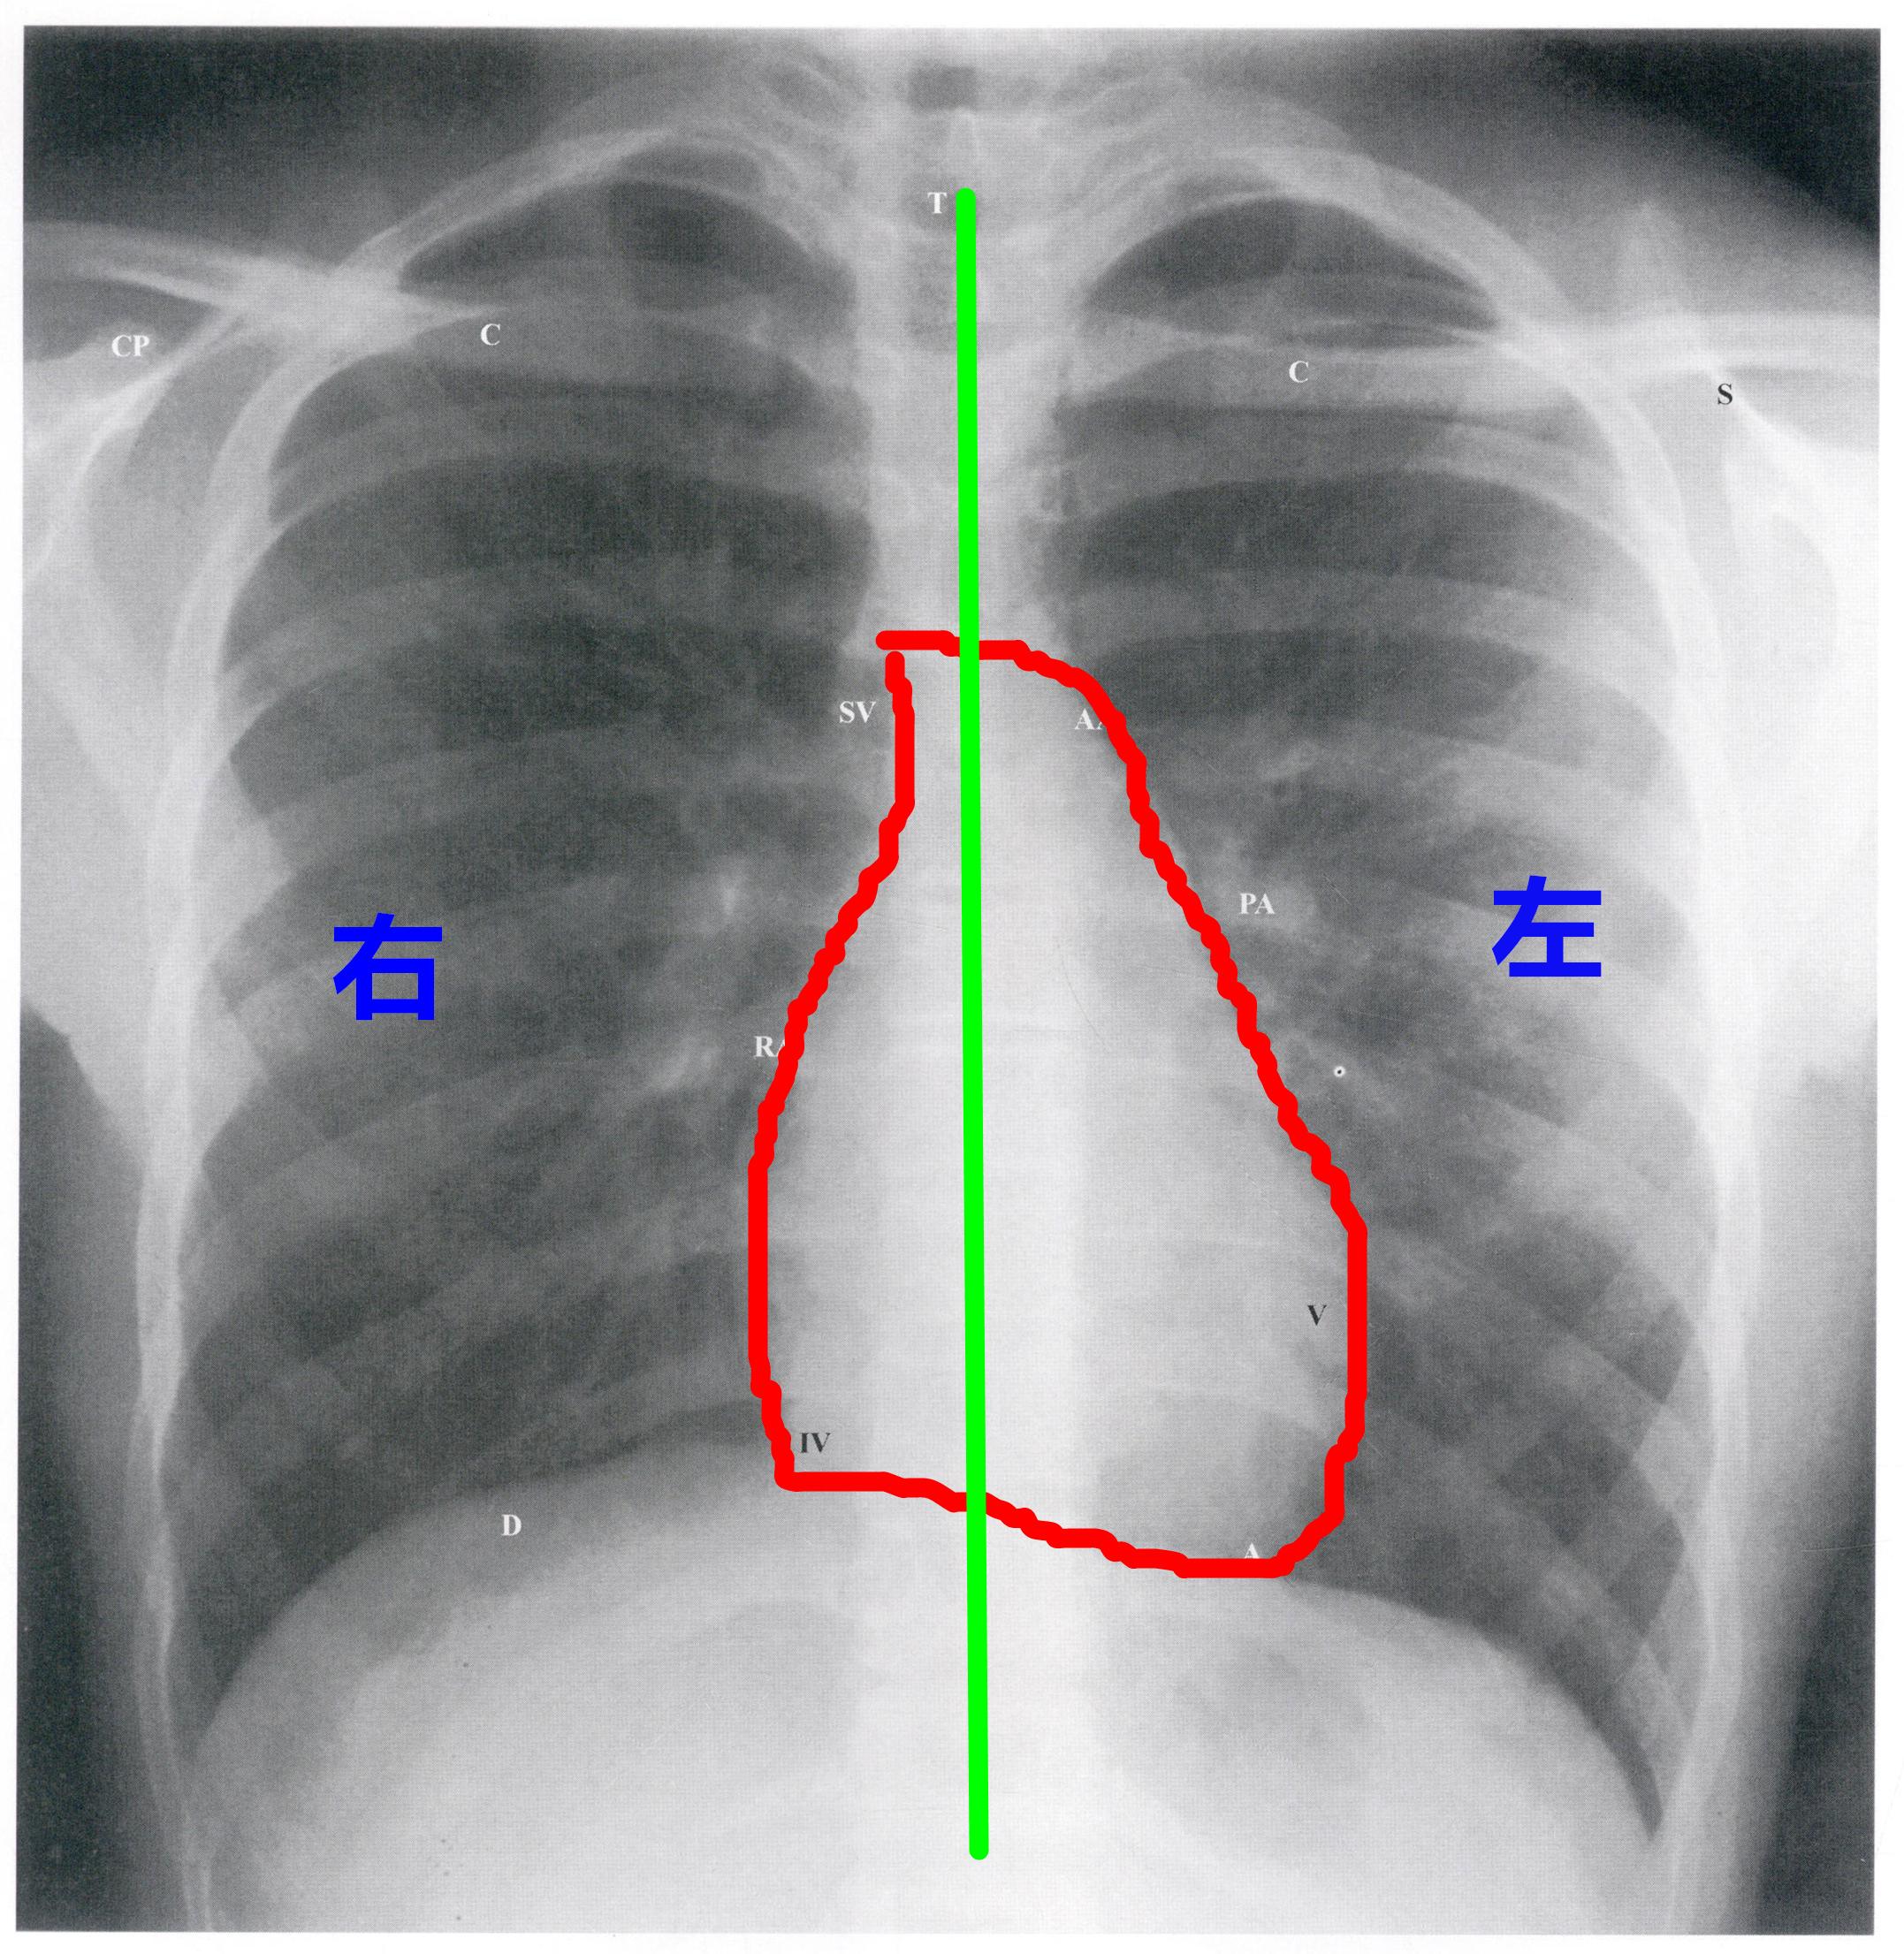

位置: 心脏 heart 心位于胸腔内,左 右两肺之间的中纵隔内, 以胸骨

大部分人是左位心脏,也就是偏于胸骨后偏左侧.

为什么心脏明明在两肺之间并不是在胸腔左侧却都说心脏在人体左侧呢?